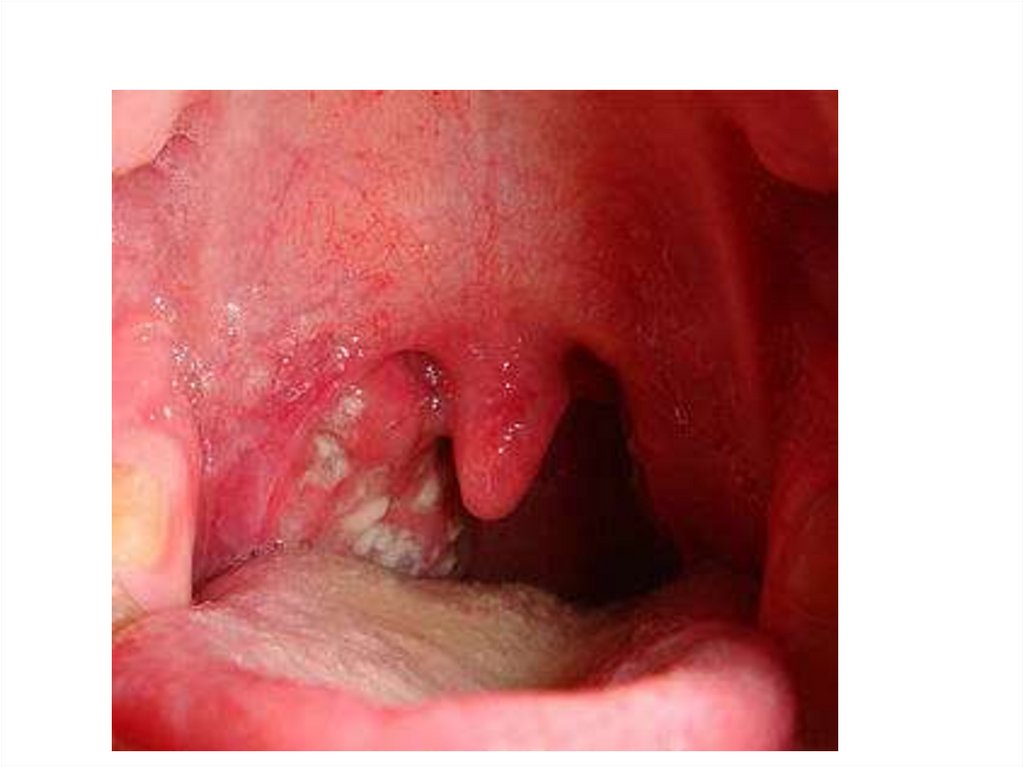

Фарингоскопические признаки

ангины Симановского-ПлаутаВенсана

• Язвенно-некротическая ангина, характерно одностороннее

поражение миндалины

• Характерными и отличительными признаками язвеннонекротической ангины являются:

• некротические изменения поверхности, как правило, одной

небной миндалины;

• формирование на поверхности миндалины эрозии, дно которой

выстлано тонкой фибринозной мембраной;

• под фибринозной мембраной скрывается участок некроза тканей